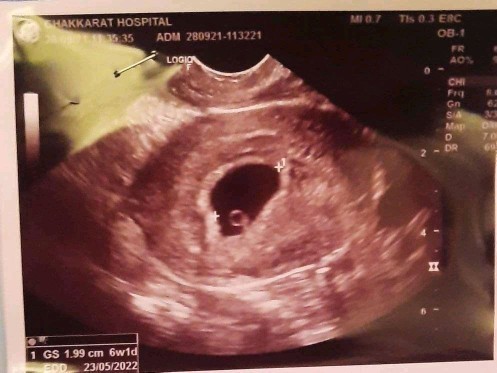

ถุงตั้งครรภ์ 6 สัปดาห์ แบบนี้ปกติไหมคะ กังวลมากเลยค่ะ

อัลตร้าซาวด์แล้วเจอแต่ถุงตั้งครรภ์แบบนี้ปกติมั้ยคะ

ขนาดถุงตั้งครรภ์ 6 สัปดาห์ มีขนาดประมาณไหนคะ แม่ๆทราบไหมคะ

น้องยังเล็กอยู่ค่ะ อาจจะเห็นแต่ถุงตั้งครรภ์